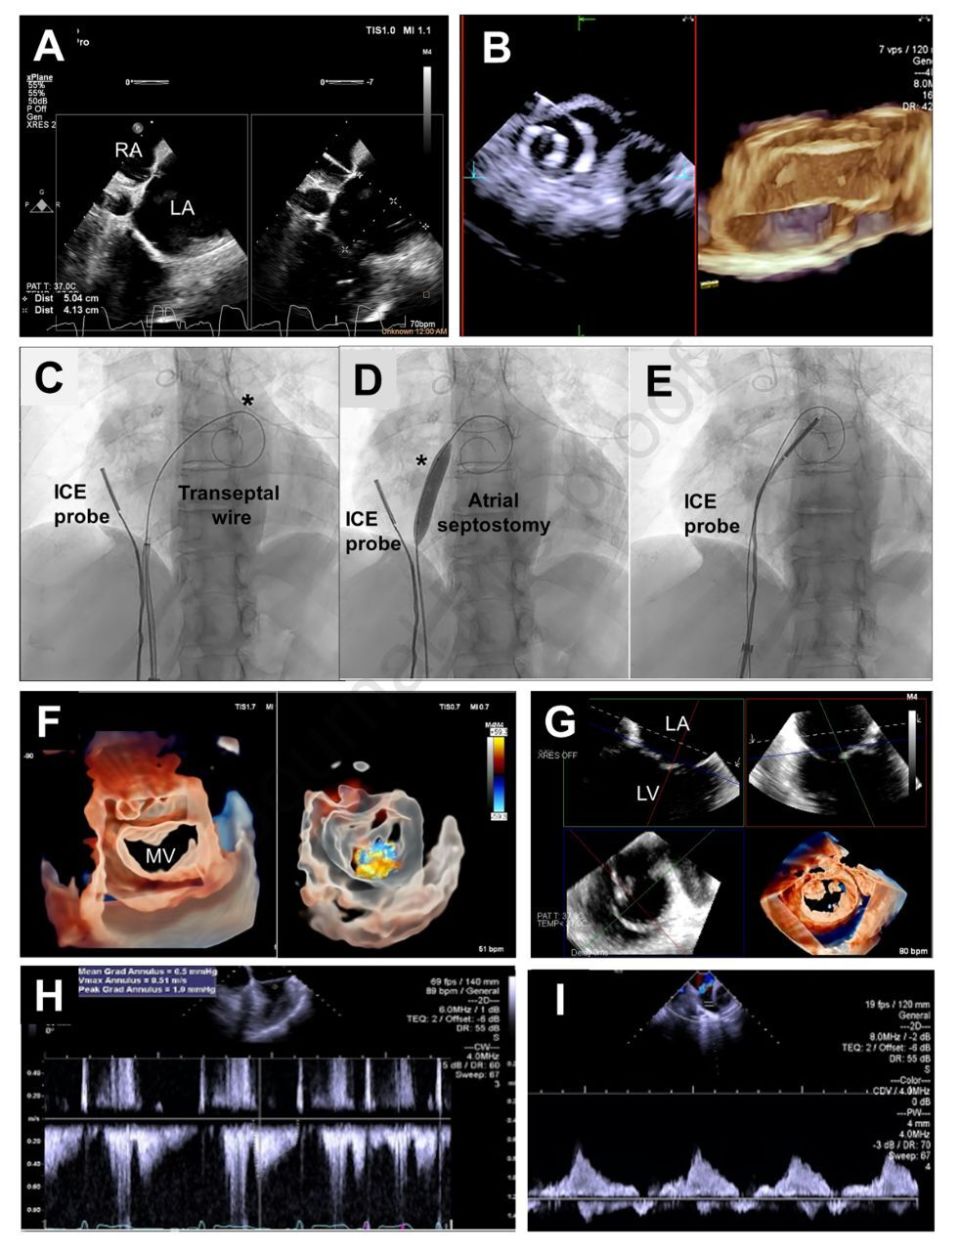

結構 超聲波

» 結構 性 超聲波 2d 3d 4d 分別 (99) 사진